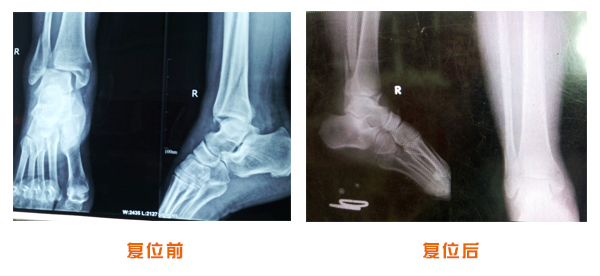

踝關(guān)節(jié)脫位骨折治療前后對(duì)比